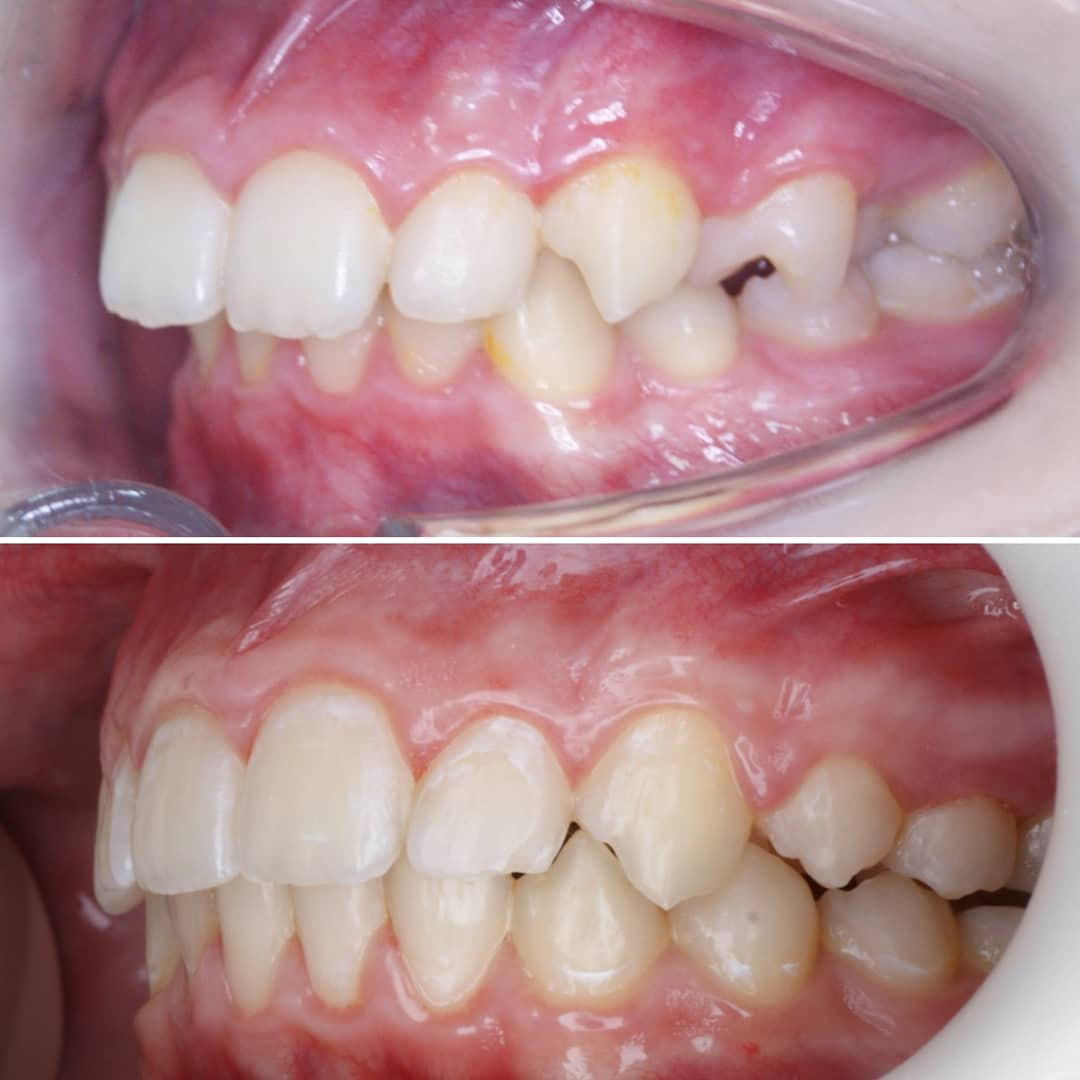

Эта фраза знакома многим ответственным родителям, которые привели на приём к ОРТОДОНТУ своего ребёнка в 5-10 лет, заподозрив проблему или понимая, что места постоянным зубам откровенно не хватает! Горькая правда в том, что брекеты - не волшебное средство от всех проблем, они "расставляют" зубы внутри сформированого объёма челюсти, но никак не влияют на её рост. Родители ждут, а тем временем драгоценное время, когда ребёнок растёт, уходит... Во взрослом возрасте приходится удалять здоровые зубы или прибегать к ортогнатической хирургической операции. 📸 На фото узкая нижняя челюсть, места постоянным зубам нет, боковые резцы прорезываются "вторым рядом".

❓Ну что? Будем ждать 12 лет? Или будем помогать ребёнку?

✅ Помогаем с помощью расширяющей дуги, пружины и зацепных элементов, которые зафиксированы на МОЛОЧНЫЕ зубы